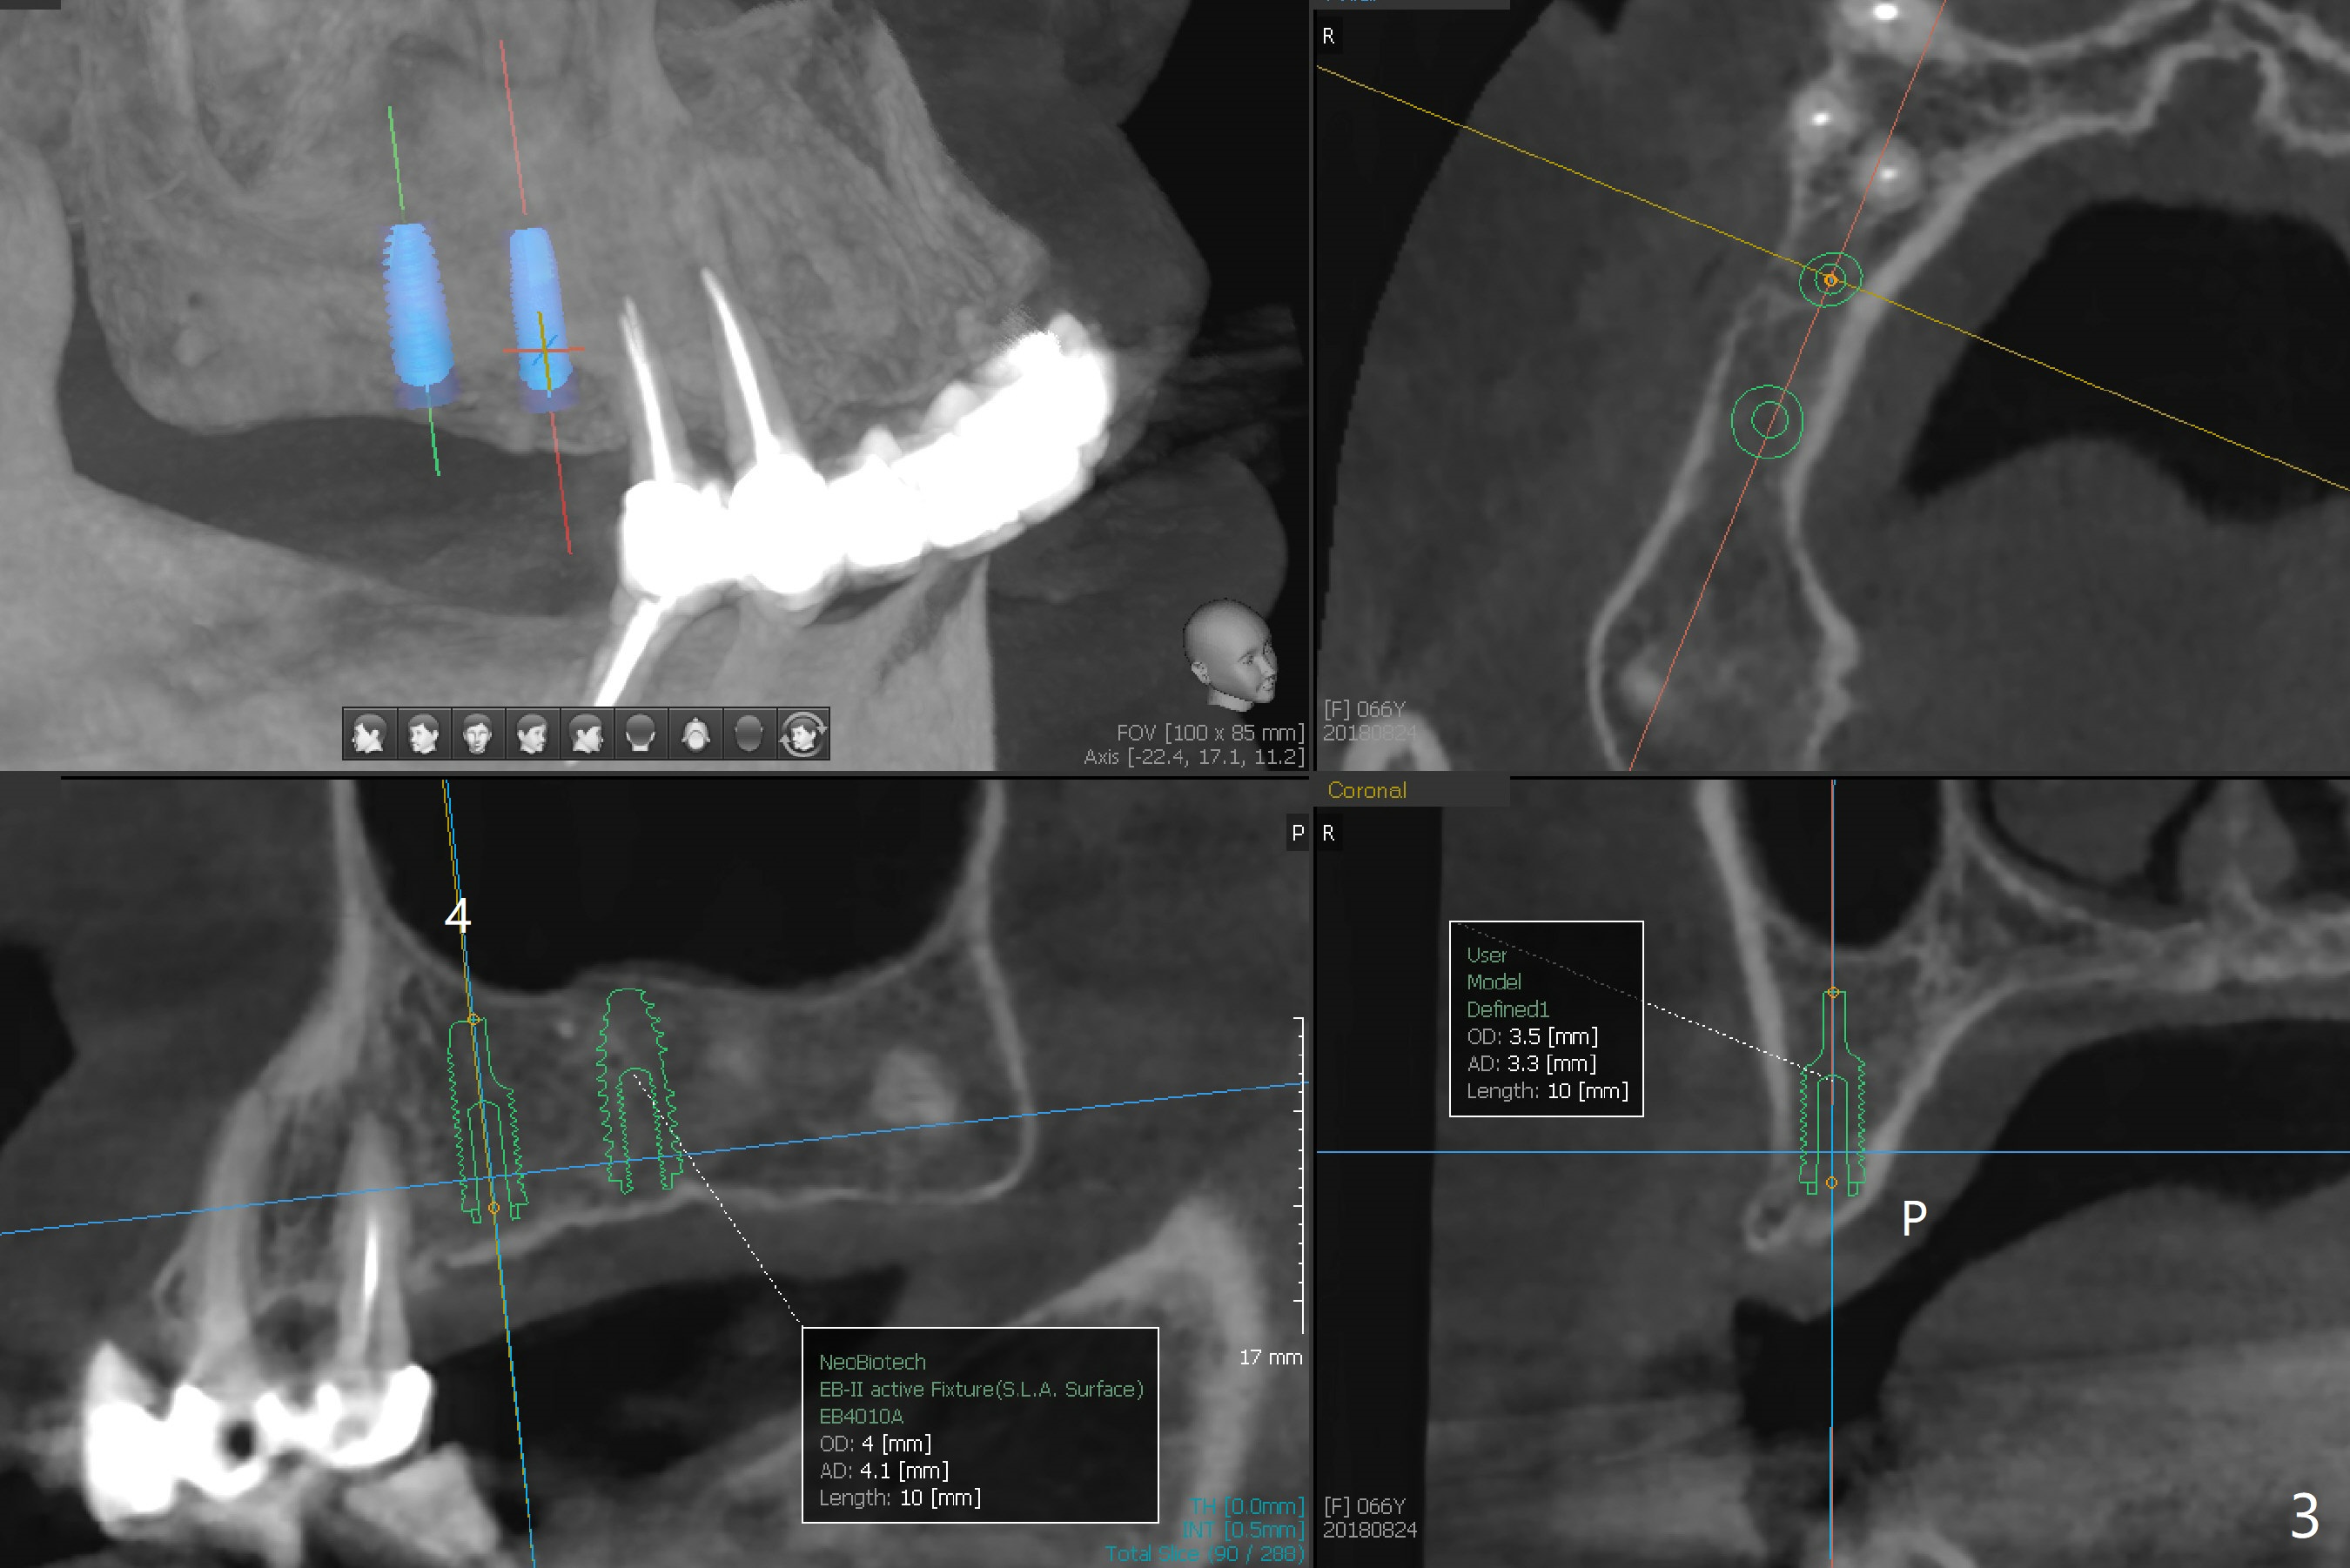

A 66-year-old woman requests implants at #3 and 4 (Fig.1). The main issue is loose bone with ~300 HU (Fig.2,3). Underprep must be a solution.